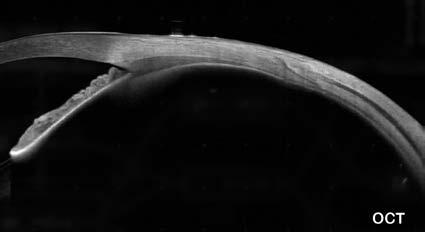

26 ¿Sabe cuál es la prevalencia de quistes en el sulcus ciliar de sus pacientes miopes? Relevancia en implantes fáquicos de cámara posterior

Autor: Dr. Germán R. Bianchi

Sin embargo, hay problemas que pueden evitarse, especialmente en el ámbito de nuestra actividad profesional. Un ejemplo de ello es la presencia de quistes de cuerpo ciliar, cuya existencia puede complicar los resultados en la implantación de lentes intraoculares fáquicos. Tal como explica el doctor Germán Bianchi, estos problemas pueden detectarse y evitarse mediante un examen preoperatorio con UBM.